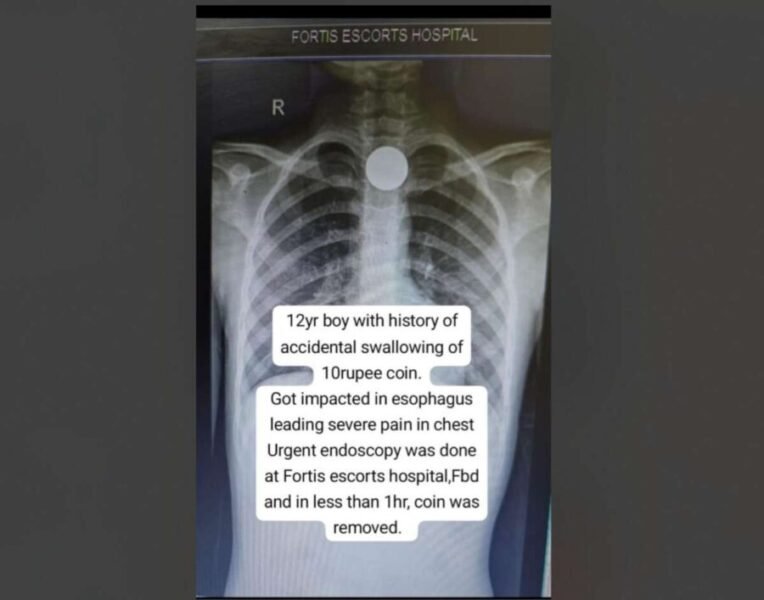

Faridabad, 03 October 2025: A 12‑year‑old child was rushed to the emergency department at Fortis Escorts Faridabad after accidentally swallowing a ₹ 10 coin. The coin, measuring nearly 27 mms in diameter, was lodged in the upper esophagus and was causing intense chest pain and difficulty swallowing. An X‑ray confirmed its presence in the food pipe. Led by Dr. Nirdesh Chauhan, Consultant – Gastroenterologist, Fortis Escorts Faridabad, the medical team opted for an urgent endoscopy to prevent life-threatening complications that could arise from delays, such as esophageal tears, infection, or breathing difficulties. Using specialized endoscopic tools, the medical team successfully removed the coin within an hour of the child’s arrival. The extraction itself took about 15 minutes, after which the child was discharged safely later that evening. Follow‑up inspection confirmed there was no damage caused to the esophagus.